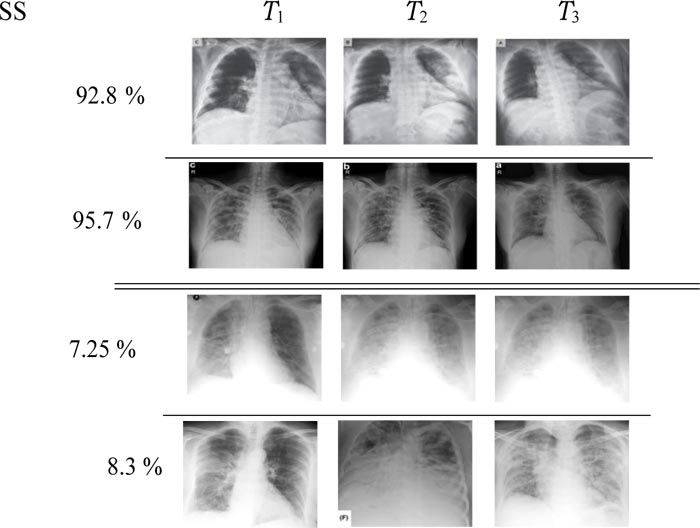

In this section, we illustrate some representative results obtained on a group of patients. These time series are made up of 3 images acquired at times T1, T2 and T3. Fig. (7) displays four-time series of Covid-19 patients, two of them (top) have survived, while the two others (bottom) are dead. For each patient, the obtained “survival score” (SS) is provided in the first column. This score is nothing but the probability predicted by the sigmoid function.

Fig. (7). Visualization of the COVID-19 classification using the propose ProgNet architecture. |

From a visual point of view, it is clear that time-series with death issues show more white areas over all images. Generally speaking, the spread of these areas increases over time. Reported SC values indicate how sure the ProgNet model is about the classification results for these time-series.